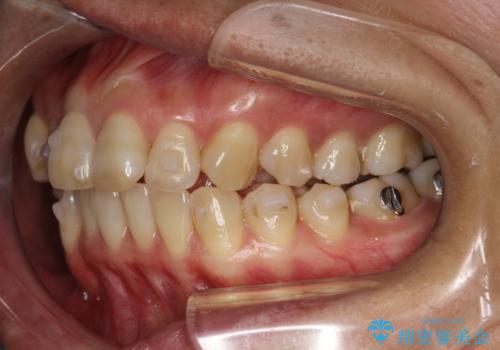

- 上下の歯並びにガタつきがあり、また、上下前歯の前後のズレが大きく上の前歯が突出しています。

インビザラインではガタつき(叢生)の改善だけでなく、上下の前後的なズレについてもアプローチが可能です。

インビザラインの特色を生かした歯牙移動計画を作成し、非抜歯にて治療を行いました。

マウスピース枚数 初回52枚 + 追加19枚 + 追加12枚

上の歯列に後方への力をかけるために、患者様には顎間ゴムをマウスピースと共に併用してもらいました。